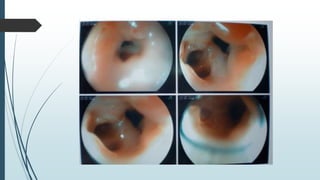

Paciente del sexo masculino, de 20 años de edad, que ingresó en agosto del

2011 al Servicio de Cirugía General por cuadro de disfagia de característica

progresiva, inicialmente a sólidos y posteriormente a líquidos, de 2 meses de

evolución, posterior a la ingesta accidental de cáusticos (soda cáustica).

Refería además astenia, anorexia y pérdida importante de peso. Se

sospecha el diagnóstico de estenosis esofágica por ingestión accidental de

cáustico. El Esofagograma (figura 1) informa retención del medio de

contraste a nivel del tercio superior esofágico, con ligera dilatación a ese

nivel, con pasaje filiforme por debajo del mismo, de 13 mm de longitud, con

irregularidad de la mucosa. La Endoscopia digestiva alta (figura 2) constató

estenosis de la luz esofágica menor a 1 cm de diámetro, con dos orificios que

podrían corresponder a procesos fistulosos, motivo por el cual se realizó una

Fibrobroncoscopía, descartándose proceso fistuloso entre el esófago y

tráquea